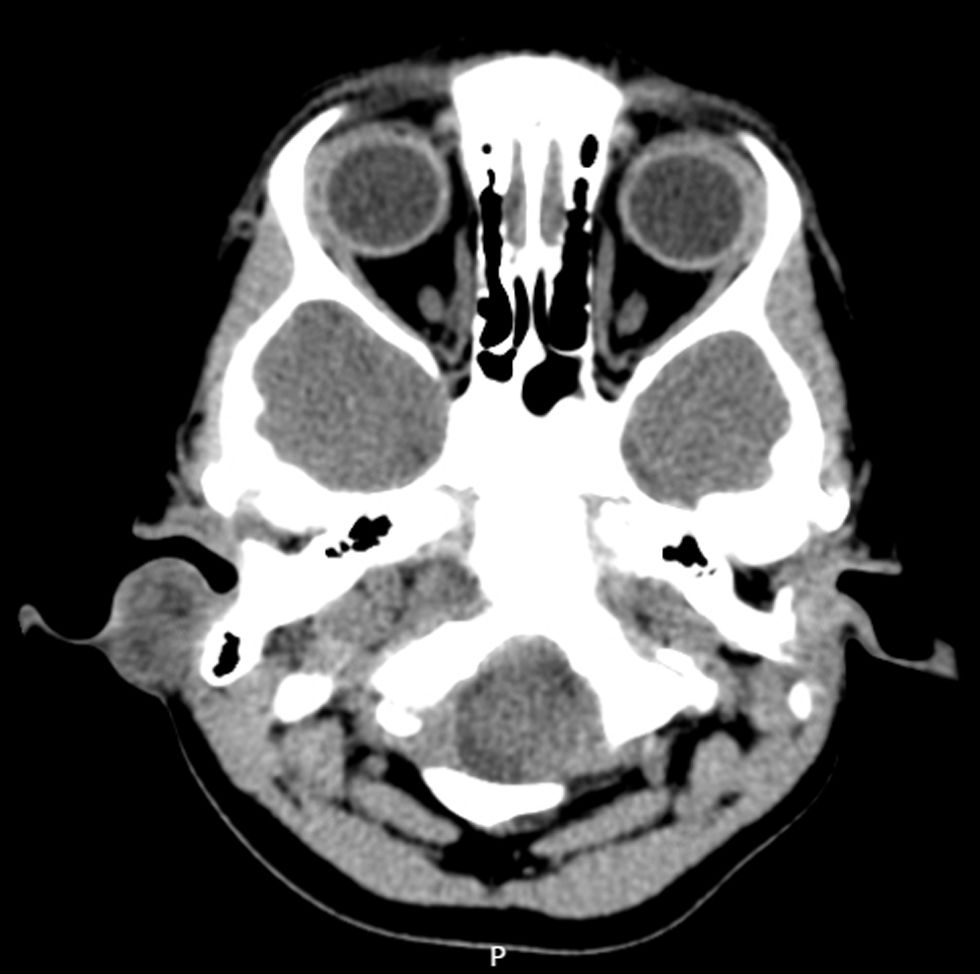

The initial diagnosis in the pediatric emergency department was otomastoiditis. An otorhinolaryngological evaluation was performed due to the poor response to empirical antibiotic therapy, which established the diagnosis of perichondritis and guided the adjustment of treatment. Clinical worsening accompanied by retroauricular swelling prompted computed tomography, which confirmed auricular perichondritis complicated by a retroauricular abscess (Fig. 2). Surgical drainage revealed a preauricular sinus, with isolation of Staphylococcus lugdunensis. The antibiotic treatment was adjusted and the patient exhibited complete clinical recovery in two weeks.